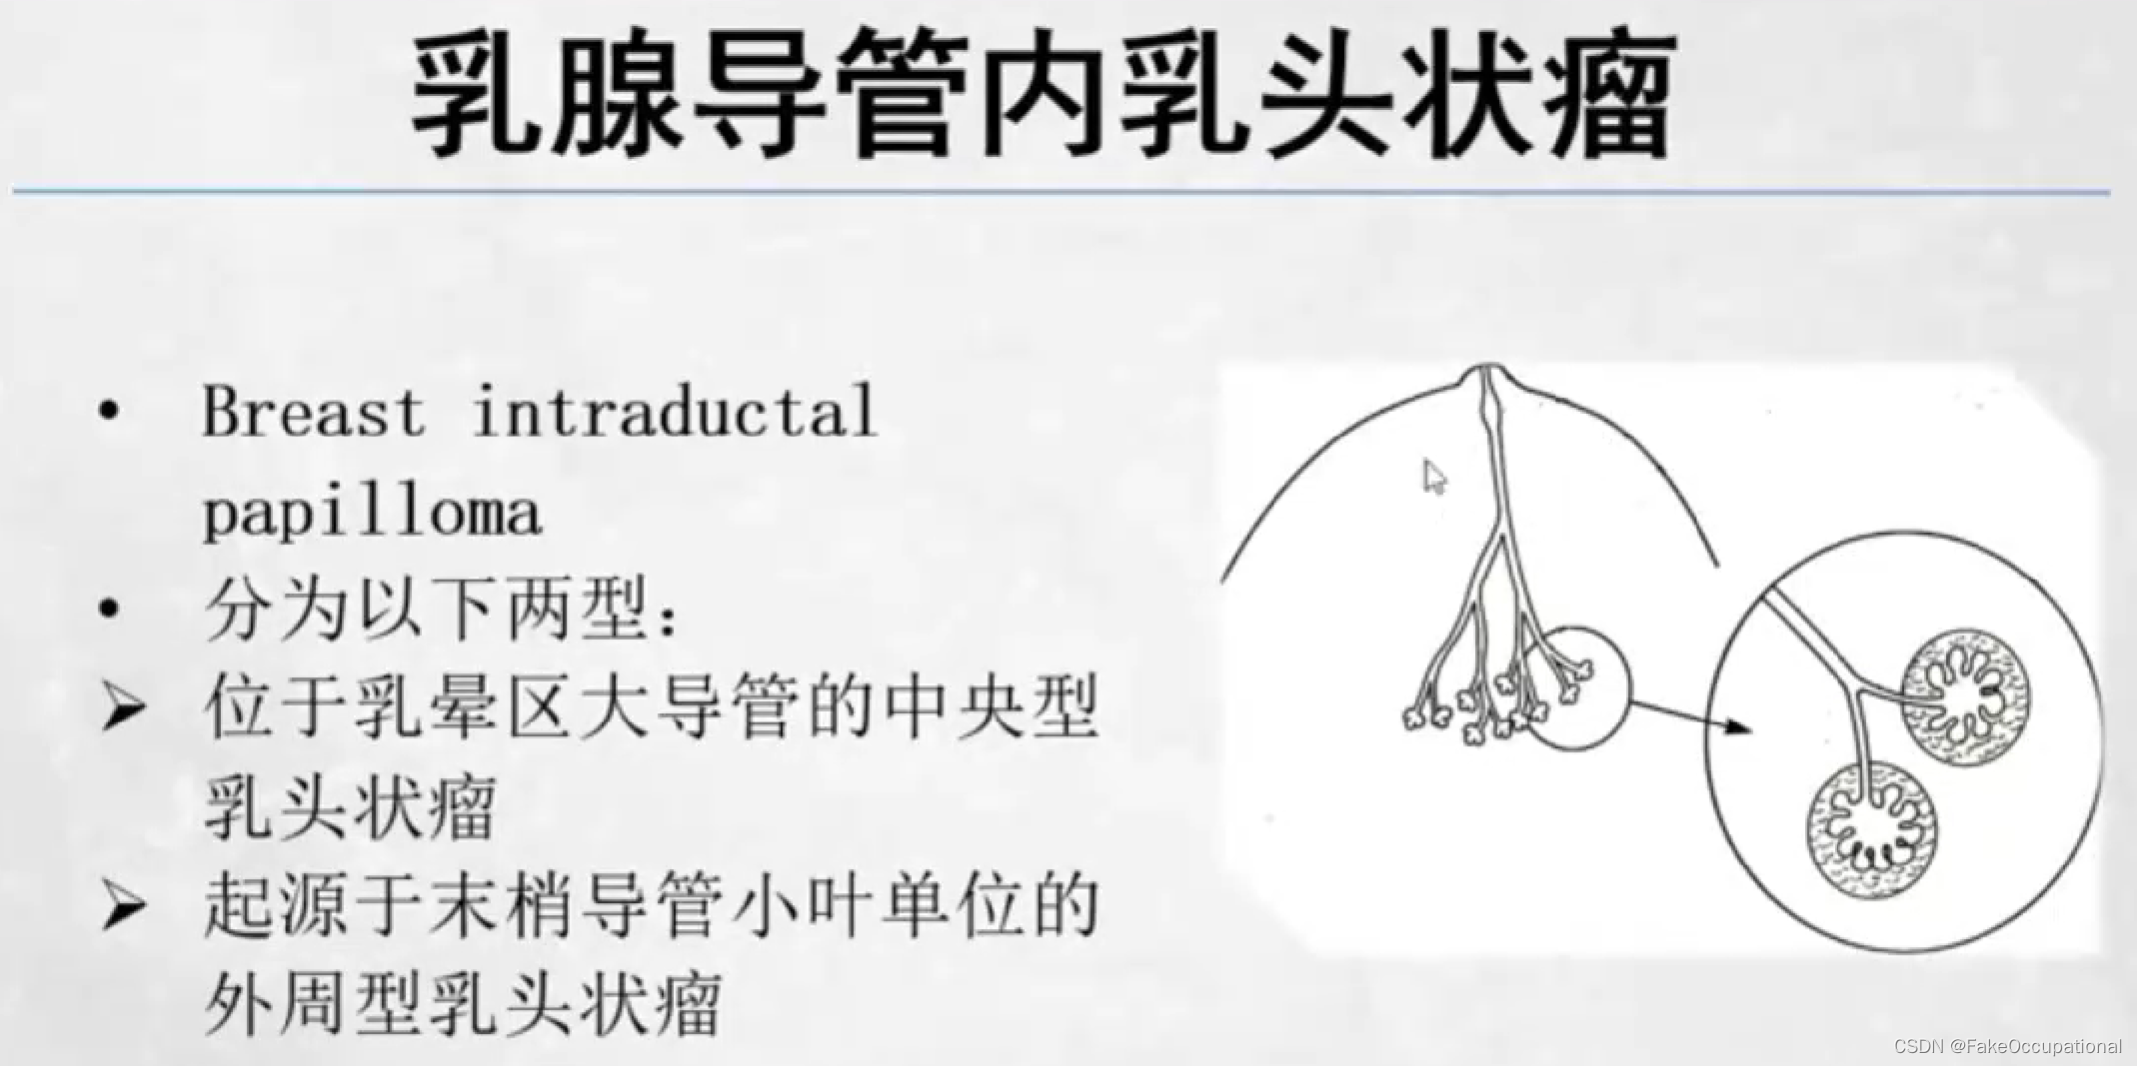

乳腺导管内乳头状瘤